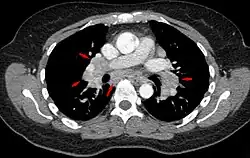

Chest radiograph changes are divided into four stages:[105]

- bihilar lymphadenopathy

- bihilar lymphadenopathy and reticulonodular infiltrates

- bilateral pulmonary infiltrates

- fibrocystic sarcoidosis typically with upward hilar retraction, cystic and bullous changes

Although people with stage 1 radiographs tend to have the acute or subacute, reversible form of the disease, those with stages 2 and 3 often have the chronic, progressive disease; these patterns do not represent consecutive "stages" of sarcoidosis. Thus, except for epidemiologic purposes, this categorization is mostly of historic interest.[28]

Hilar adenopathy especially on the person's left (AP CXR)

Hilar adenopathy especially on the person's left (lateral CXR)

Hilar adenopathy especially on the person's left (coronal CT)

Hilar adenopathy especially on the person's left (transverse CT)